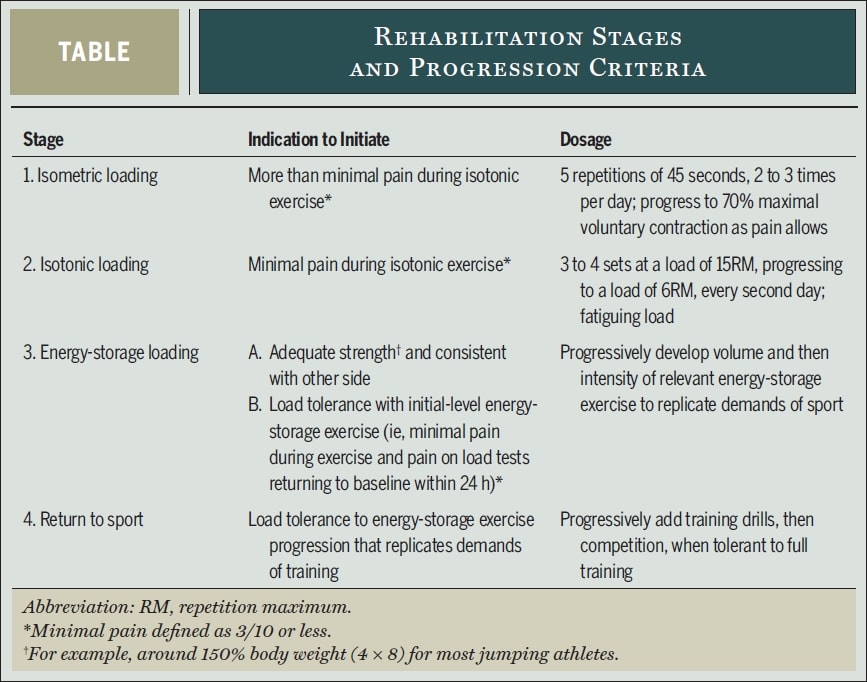

Entonces, ¿cómo podría ser un programa de resistencia pesada-lenta de este tipo? Los investigadores Peter Malliaras, Jill Cook, Craig Purdam y Ebonie Rio, expertos en tendinopatías, proponen el siguiente protocolo de rehabilitación en 4 fases basado en la evidencia en su artículo de 2015:

En primer lugar, debe modificarse la carga de las actividades de almacenamiento de energía de alta carga que agravan el dolor. En el caso de los deportistas que se encuentren a mitad de temporada, el volumen y la frecuencia de dichas actividades deberán reducirse previa consulta con el deportista y el entrenador. Se consideró aceptable algo de dolor durante y después de los ejercicios, pero los síntomas debían haber remitido en las 24 horas posteriores. En su artículo, Malliaras utilizó una repetición de sentadilla declinada con una sola pierna hasta 90 grados de flexión de rodilla o ángulo máximo permitido por el dolor como prueba de dolor-provocación para determinar la tolerancia a la carga en el día a día. Si la puntuación del dolor en la prueba de carga ha vuelto al valor basal en las 24 horas siguientes a la actividad o sesión de rehabilitación, la carga ha sido tolerada. Si el dolor empeora, se ha superado la tolerancia a la carga.

Veamos con más detalle cada etapa de la rehabilitación:

Fase 1 - Reducción del dolor: Carga isométrica

- 5 repeticiones de 45s de ejercicio isométrico de alcance medio (30-60° de flexión de rodilla) de cuádriceps con una sola pierna al 70% del MVIC 2-3x/día.

- La resistencia debe aumentarse tan rápido como se tolere.

- Sentadilla española

- Abordar otros déficits de fuerza a lo largo de la cadena cinética

Etapa 2 - Restauración del volumen y la fuerza musculares e inducción de la adaptación tendinosa: Carga isotónica

- Cuando los cuádriceps pueden cargarse isotónicamente sin dolor superior a NRS 3/10, puede iniciarse esta fase.

- Actividades de resistencia lenta intensa entre 10° y 60° de flexión de la rodilla inicialmente y progresión hacia y más allá de 90° de flexión según lo permita el dolor. Entre ellas se incluyen las prensas de piernas, las sentadillas, las sentadillas hack, las sentadillas divididas y las extensiones de rodilla sentadas. Inicialmente con dos piernas y progresar hacia una sola pierna tan pronto como el dolor lo permita. Kongsgaard et al. utilizaron de 3 a 4 series cada dos días a una resistencia correspondiente a 15RM y progresaron hasta 6RM. Continúe con los ejercicios de la fase 1 los días entre los ejercicios de resistencia lenta pesada.

Etapa 3- Carga de almacenamiento de energía: Aumenta la tolerancia a la carga y mejora la potencia

- Cuando se consigue una buena fuerza y el deportista tolera cargas con una sola pierna de alrededor del 150% del peso corporal (por ejemplo, 4 series de 8 repeticiones de press con una sola pierna), se puede iniciar esta fase si no se observa dolor más allá de NRS 3/10 en las 24 h posteriores al entrenamiento.

- La iniciación puede ser una prensa bilateral de piernas con cargas de 3 veces el peso corporal (o 1,5 veces en caso de una sola pierna), ya que esto ejerce una fuerza rotuliana correspondiente a las fuerzas observadas durante el aterrizaje de un salto vertical.

- Secuencias de saltos con paradas, saltos y aterrizajes, aceleraciones y desaceleraciones, cortes y cambios de dirección

- El volumen (el número de saltos, contactos) progresó antes que la intensidad (altura, velocidad)

- Realizar cada tercer día y continuar con carga isométrica y carga isotónica cada segundo y tercer día.

Etapa 4 - Vuelta al deporte

- Regreso gradual al entrenamiento y la competición, en el que inicialmente el entrenamiento se corresponde con el volumen y la intensidad de los ejercicios de la fase 3 y progresa hasta un volumen y una intensidad acordes con la situación específica del deporte.

- Mantenimiento de los ejercicios de la fase 2 al menos dos veces por semana y, eventualmente, de los ejercicios de la fase 1 antes o después del entrenamiento.

Tenga en cuenta que todo el proceso de rehabilitación puede ser lento y durar a veces más de 6 meses. Un estudio de Bahr et al. (2014) descubrieron que solo el 46 % de los atletas con tendinopatía rotuliana pudieron volver a entrenar a pleno rendimiento y no sufrieron dolor tras un programa de entrenamiento excéntrico durante 12 meses.